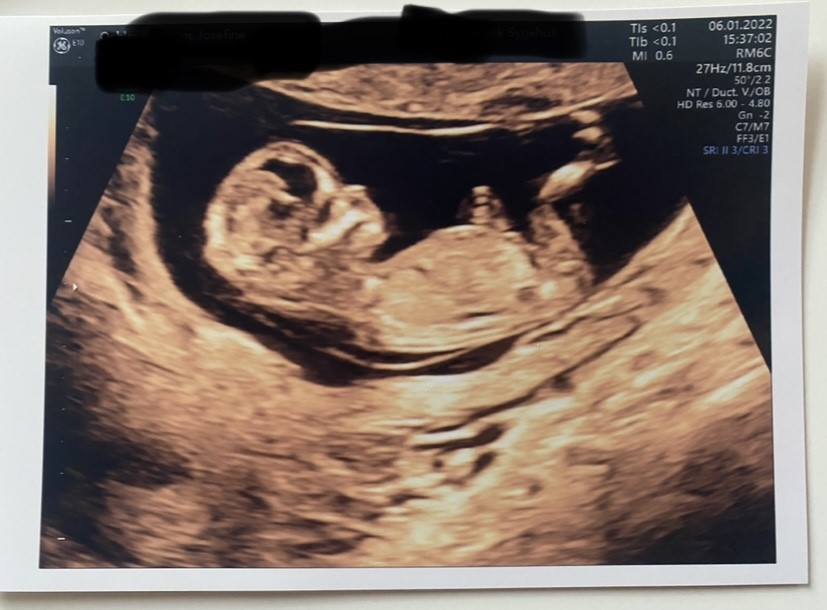

Hvordan det? I følge nub teorien er det jo uden tvivl en dreng.

Ja, hvis det  er nubben, vi ser, så er det højst sandsynligt en dreng, da tydelige drenge sjældent viser sig at være piger - det er mere omvendt, at pige-lignende nubs kan rejse sig senere hen.

Men har du andre billeder? Jeg synes der er for mange ubekendte til at vi kan analysere, fordi vi jo ikke kan garantere, at det er nubben og ikke lårben, man ser... så er det jo bare spildte kræfter og tanker selvom man jo godt må gætte for sjov..

Det har jeg gjort og de sagde at det helt sikkert er en dreng

I forhold til at du spørger virker du meget sikker på at du selv kender svaret

Jeg tror heller ikke at det du kigger på er nuben. Jeg synes det ligner en pige. Og tror at det du tænker er nub i virkeligheden er lidt af navlestrengen.

Pas nu på at du ikke overbeviser dig selv om noget som ingen af os reelt set ved. Inkl. Facebook-gruppen

Jeg er allerede overbevist. Det var jeg allerede efter scanningen hvor jeg også synes det lignede tydeligt en dreng.

Men min kæreste vil have det bekræftet ved 20. Ugers scanningen nu.

Okay, men så har du jo nok svaret - deres admins virker til at de sjældent tager fejl, ellers siger de til, hvis de er usikre/påpasselige med svaret   Tillykke med din dreng